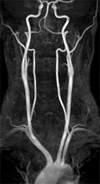

MRA (Magnetic Resonance Angiography)

Magnetic resonance imaging (MRI) is a method of producing extremely detailed pictures of body tissues and organs without the need for x-rays. The electromagnetic energy that is released when exposing a patient to radiofrequency waves in a strong magnetic field is measured and analyzed by a computer, which forms two- or three-dimensional images that may be viewed on a TV monitor. MR angiography (MRA) is an MRI study of the blood vessels. It utilizes MRI technology to detect, diagnose and aid the treatment of heart disorders, stroke, and blood vessel diseases. MRA provides detailed images of blood vessels without using any contrast material, although a special form of contrast material is often given to make the MRI images even clearer. The procedure is painless, and the magnetic field is not known to cause tissue damage of any kind.

- MRA is also used to detect disease in the aorta and in blood vessels supplying the kidneys, lungs and legs